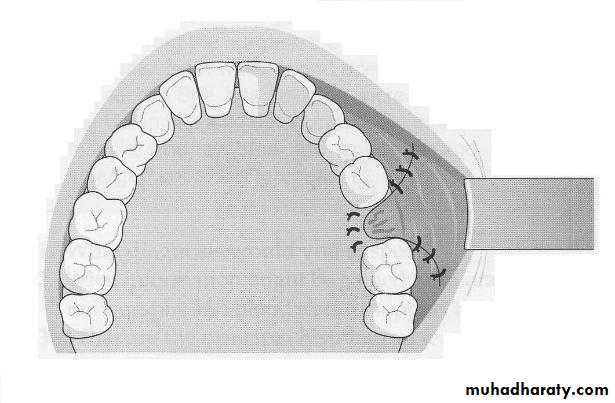

Closure of accidental oro-antral communication in the dentulous arch (1) Incisions are made around the teeth and antral opening. A relaxing incision is made on the palate (2) Mucoperiosteal flaps raised and the buccal and palatal alveolar walls are reduced with rongeur, (3) Interrupte suturing done

Diagramatic illustration of advancement buccal flap